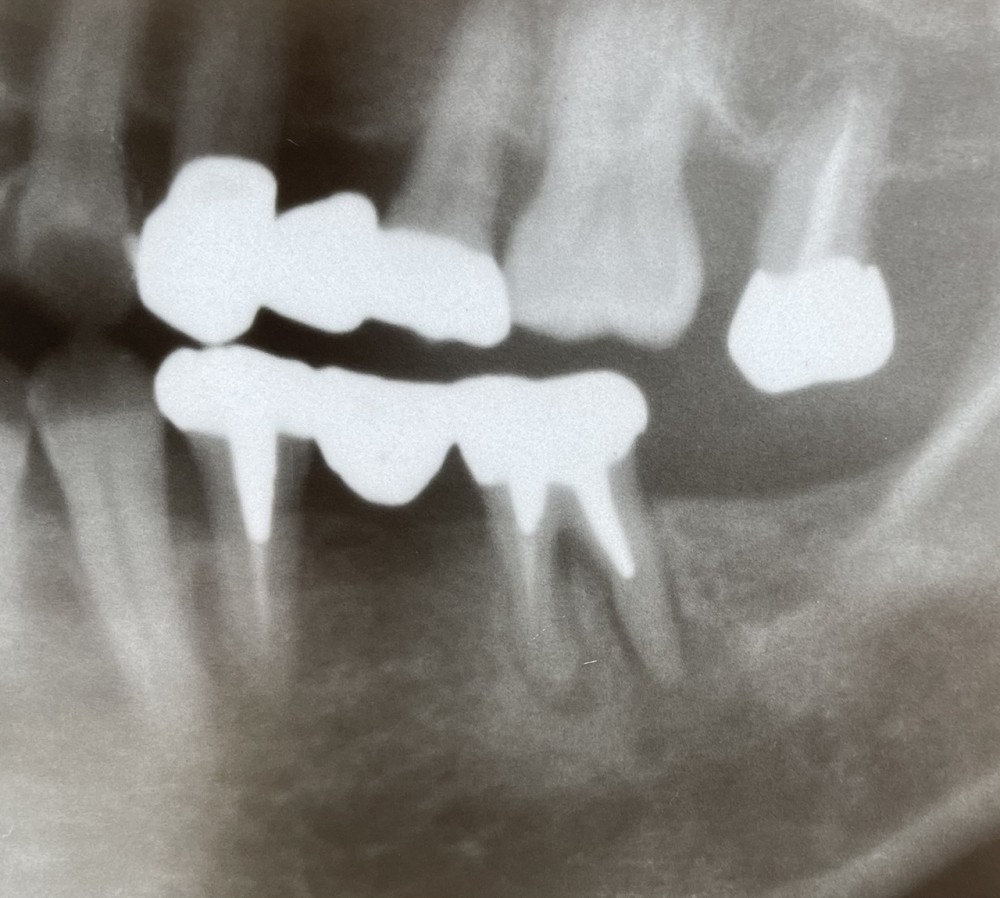

下のレントゲン写真をご覧ください。

当該の歯に激しい痛みがあります。

ブリッジの支台になっていて、金属製の土台が深く入り、根管内のお薬の入り方が甘く、根先の歯槽骨の吸収が見られます。